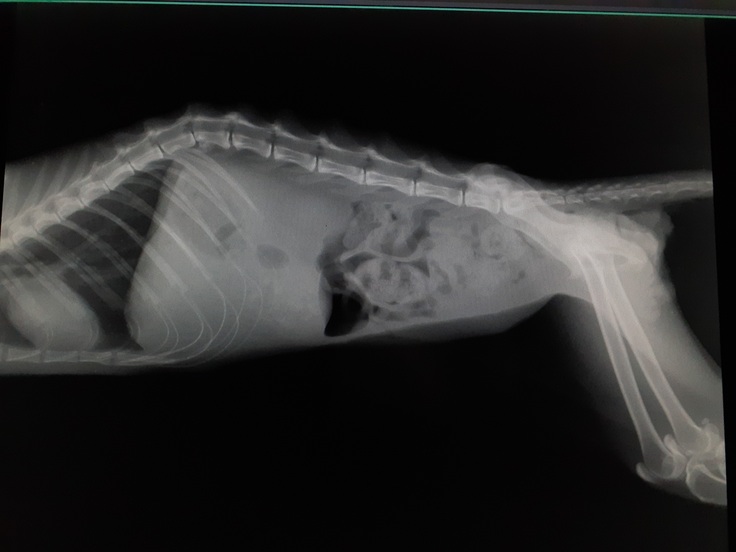

下半身不随の状態もレントゲンにて確認してきました。

背骨の3つと4つ目の骨が骨折していました。

既にねこ活にいる下半身不随の【くるみちゃん】は3つ目の骨折でしたのでそれよりは酷い状態を確認いたしました。

病院では大分酷い事故であったことを血液検査、レントゲンにて説明していただきました。